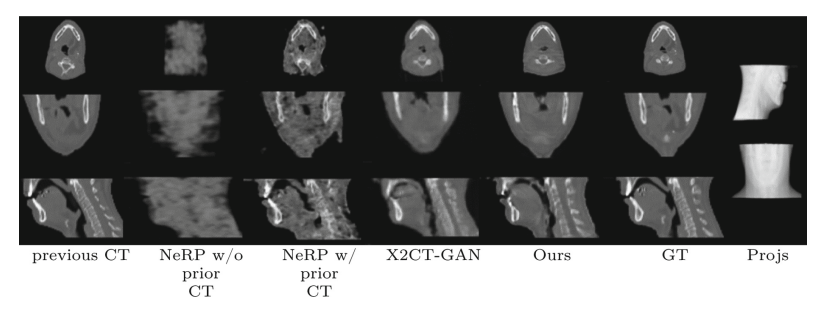

For the visual result which listed in the figure below, it is evident that the X2Vision method demonstrates superior performance in reconstruction. For instance, when compared to other methods, distinct spinal structures are clearly visible in the X2Vision reconstructions. In contrast, the results from other methods predominantly show noise in the corresponding areas, underscoring the significant improvements achieved by the X2Vision approach.

Figure12: Visual results of X2Vision and other methods